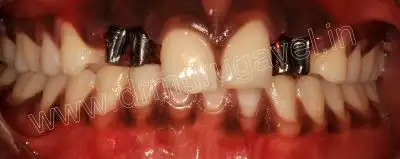

On clinical examination it was looking like retained deciduous teeth present in relation to 12,13,22 and 23 region.

pre-op front view

Clinical examination